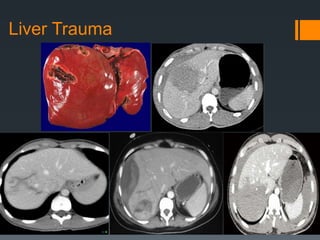

Liver Trauma

Bile duct injury

https://radiopaedia.org/cases/traumatic-liver-and-bile-duct-

injuries